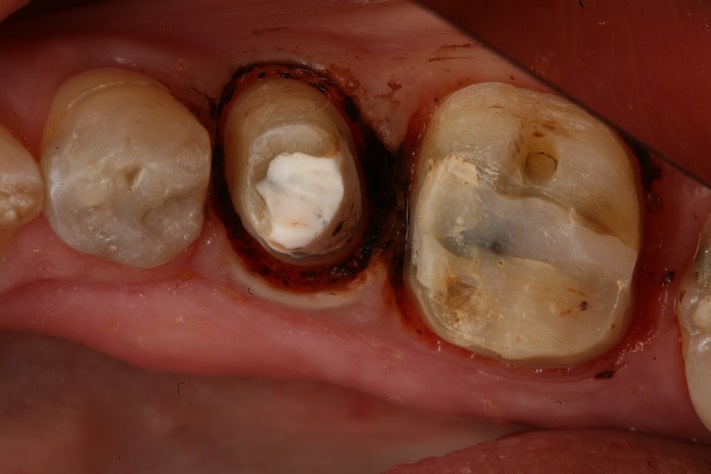

Gary Umeda #19-20 prep